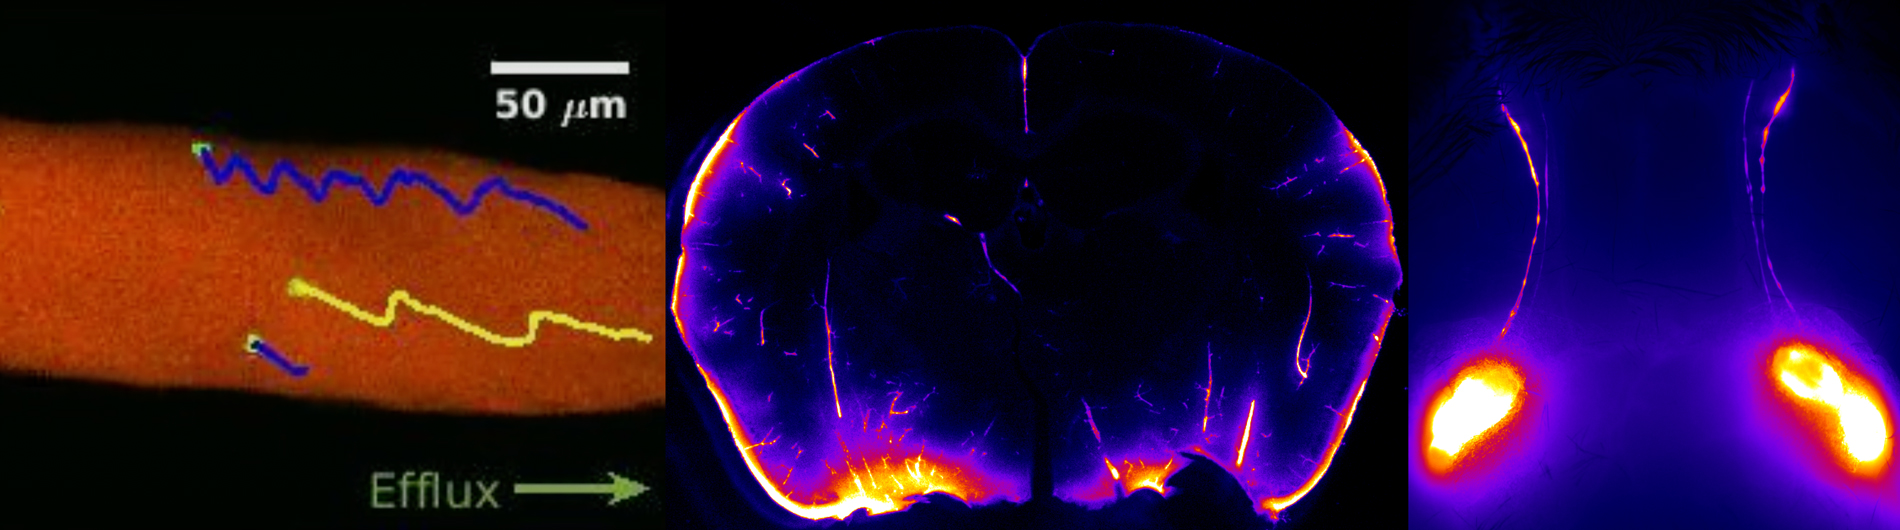

Our lab focuses on "Diseases of Brain Fluid Homeostasis," with the goal of understanding how the brain maintains fluid balance and clears waste to support overall health. We investigate the intricate processes involved in cerebrospinal fluid (CSF) production, circulation, and clearance, with a particular emphasis on the role of cervical lymphatic vessels (cLVs) in facilitating brain waste removal. These vessels act as critical pathways for transporting waste-laden CSF to lymph nodes, and their dysfunction can have significant implications for neurological health.

We also study the choroid plexus, a specialized structure that produces CSF, examining how its regulation and dysfunction contribute to conditions such as hydrocephalus, where fluid accumulates abnormally in the brain. Our research extends to exploring the impacts of impaired brain fluid homeostasis in acute and chronic conditions, including stroke and Alzheimer's disease. In Alzheimer's, disrupted fluid clearance is believed to contribute to the accumulation of toxic proteins, such as amyloid-beta, which are central to disease progression.

By combining advanced imaging and molecular biology techniques, our lab seeks to uncover new therapeutic approaches. We aim to identify strategies to restore or enhance brain fluid clearance mechanisms, offering potential treatments for a wide range of neurological disorders.

- Artificial intelligence velocimetry reveals in vivo flow rates, pressure gradients, and shear stresses in murine perivascular flows.; Proceedings of the National Academy of Sciences of the United States of America; Vol 120(14), pp. e2217744120. 2023 Mar 29.

- Loss of aquaporin-4 results in glymphatic system dysfunction via brain-wide interstitial fluid stagnation.; eLife; Vol 12. 2023 Feb 09.